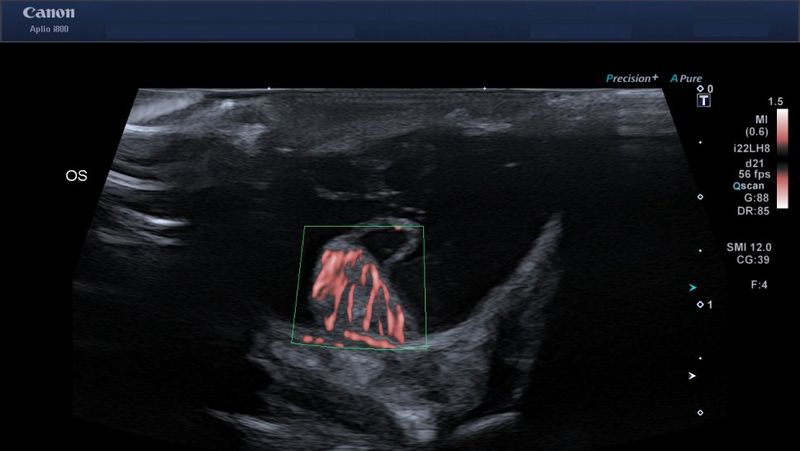

The Aplio i800 ultrasound also offers SMI or ‘Superb Microvascular Imaging’, which is another unique and fascinating technology. The SMI software is used to visualise blood flow and can be used in a wide range of settings, from liver and kidney tumours to ophthalmology, and can even give a detailed view of the pecten (a structure of blood vessels) in both reptiles and birds’ eyes. This technology is gaining momentum in many other areas of pet imaging as “SMI enables us to evaluate perfusion in the smallest body parts, such as the intestines of small rodents, or the adrenal gland or lymph nodes of ferrets, with really subtle low blood flow.”